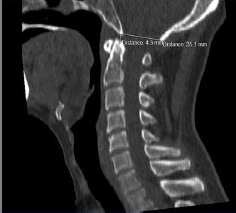

Introduction: The odontoid process is the central pillar of craniovertebraljunction. It is assessed by lateral cervical spine and base of skull radiographs which however have diagnostic challenges due to the complexity of the anatomy. Modern-day Computed Tomography (CT) offers excellent bony detail and its ability to reconstruct the acquired CT data into various imaging planes makes the assessment of the cranio-cervical junction easy and more accurate. The standard skull base lines (Chamberlain’s and McRae’s lines) are used in the evaluation of the craniovertebral junction. They help to illustrate the degree of deformity in patients with basilar impression and aid in surgical decisions with regard to decompression, fixation and stabilization. These measurements are also used as guides in the conservative follow up of patients or those who are surgically managed. The Aim of The Study: To evaluate the relationship of the odontoid tip of C2 to the standard skull baselines of Chamberlain’s and McRae’s on computed tomography in symptomatic and asymptomatic patients. Materials and Methods: Reformatted midline sagittal CT images of 150 patients (M-68,F-82) were retrospectively evaluated. The shortest perpendicular distance was measured from the Chamberlain’s and McRae’s baselines for each subject to the odontoid tip. Results: The most common age group in male is 41-50 and female 31-40 years. The mean position of the odontoid process was 2.65 mm below Chamberlain’s line (median 2.7 mm, SD 0.21mm) and 4.6 mm (median 4.6 mm, SD 0.19 mm) below McRae’s line.There was no statistically significant difference in measurements between male and female patients. Conclusion: Imaging of this small structure to reach a specific diagnosis continues to be a challenge for radiologists. Multiplanar imaging with CT allows more detailed evaluation of bony and soft tissue structures. Adequate knowledge of development, complex anatomy, various disease processes, topographic relationships of odontoid with respect to CVJ and craniometry in association with the appropriate clinical background can provide a meaningful diagnosis. These results provide the mean of normal distance from the odontoid process to the standard skull base lines on CT. This study can be used as a base line data to access skull base problems.